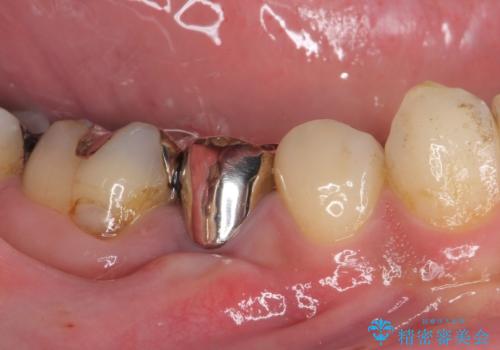

当初は根管治療を再度行うことで痛みが引くことを期待しましたが、該当歯の歯周ポケットが局所的に深くなっていることから、歯に穴が開けられているか破折している可能性が疑われました。

歯肉を開いたところ、周辺の歯槽骨は全て炎症で失われ、破折と同等の穴が開けられていることが分かったため、抜歯を行いフルジルコニアブリッジにて補綴することとしました。